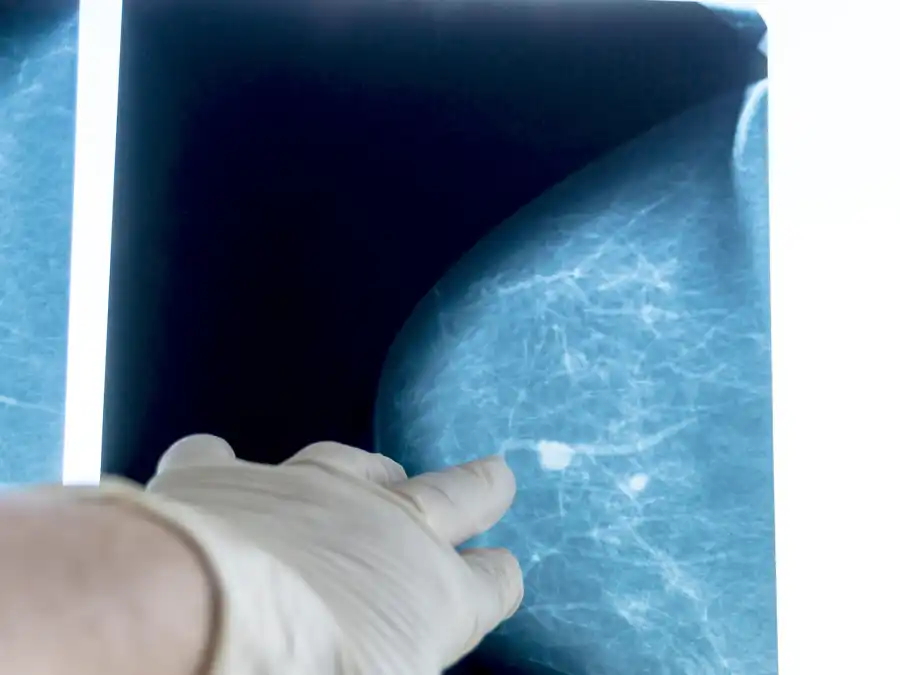

Determinar a natureza dos cistos mamários envolve uma avaliação durante o exame clínico dos seios. No entanto, esse exame por si só não pode com certeza distinguir se o nódulo é sólido ou um cisto cheio de líquido. Para esclarecer essa questão, o uso de ultrassonografia e mamografia, que são técnicas de imagem, é fundamental.

Independentemente do número ou do tamanho, cistos mamários simples, embora geralmente benignos, devem ser monitorados regularmente.